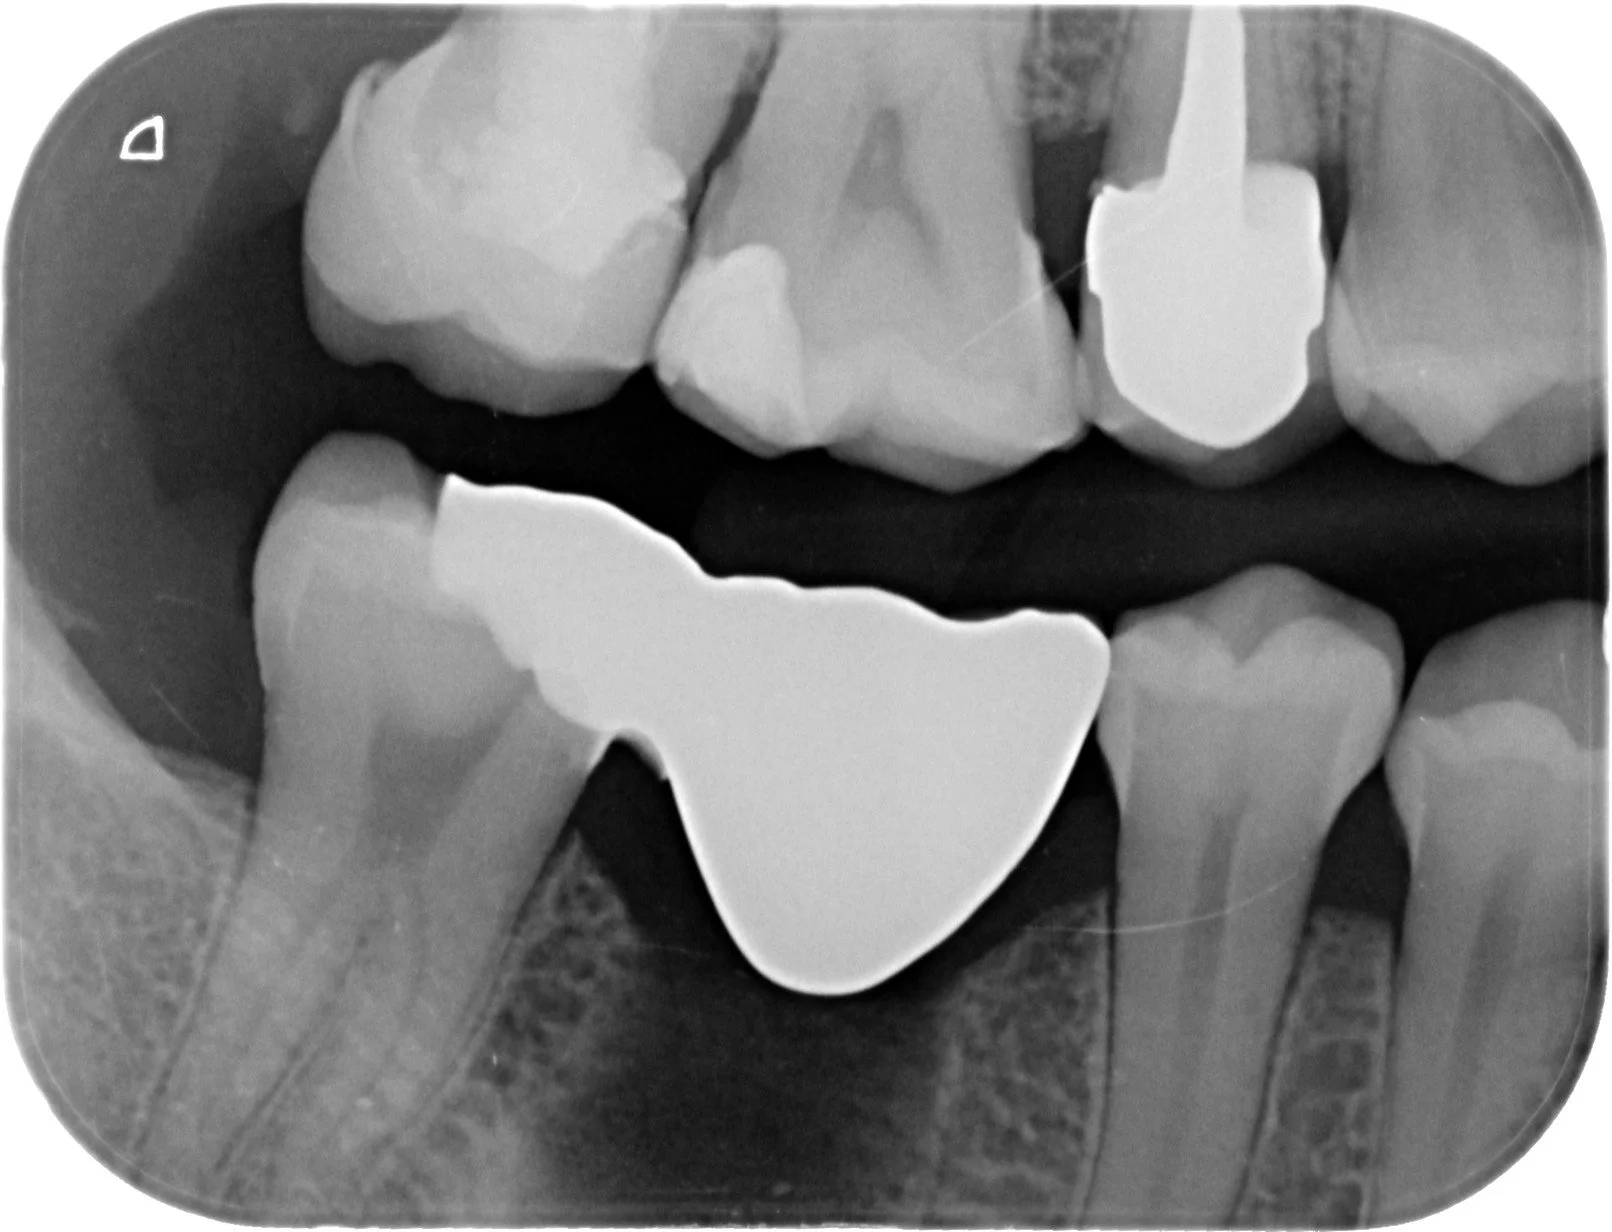

Relativement récents, les bridges collés cantilever postérieurs constituent une alternative fixe, fiable et véritablement minimalement invasive aux implants dans les secteurs postérieurs. Cette thérapeutique qui repose sur des indications bien précises est parfois débattue avec passion sur les réseaux sociaux ou dans les congrès scientifiques. Cependant des études cliniques existent, tout comme des recommandations validées dans des journaux internationaux. Leur succès repose sur des préparations et des principes biomécaniques rigoureux, pourtant simples à intégrer au quotidien. Cette intervention propose un guide clair et opérationnel incluant indications, étapes clés, protocoles d’adhésion et réglages occlusaux pour les mettre en œuvre avec confiance et reproductibilité.